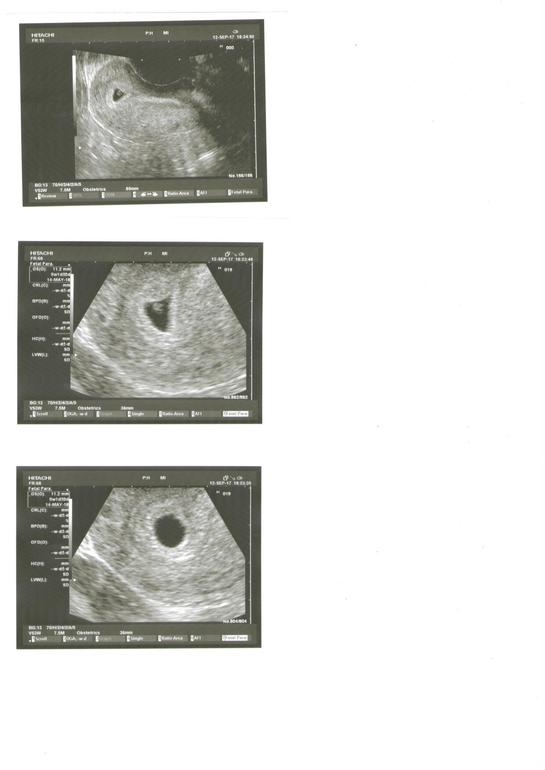

Вчера была у врача. В полости матки определяется плодное яйцо диаметром 11,2 мм. Эмбрион визуализируется. Желточный мешочек 2,9 мм. Сказали, что эмбрион прячется, поэтому серцебиение еще не услышали, маленький срок, сказали приходить через 10 дней. Поставили срок 5н1д